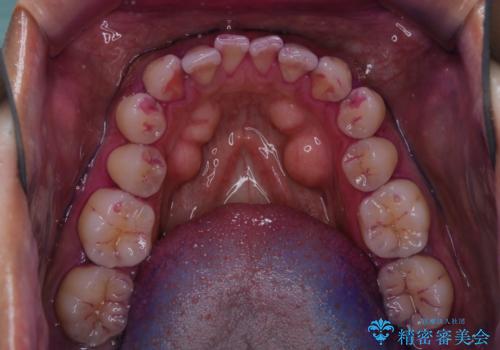

今後、ホームホワイトニング予定との事で、クリーニングPMTC(保険適応外)60分コースを行いました。汚れを取り除き、ご自身の本来の歯の表面になることでツヤがでます。

歯の表面に汚れがついたままホワイトニングを行うと、ホワイトニングの効果が出づらいことがあります。

汚れがついたままだと、虫歯・歯周病・口臭などの原因にもなります。歯科医院での、定期的なクリーニングを行うことが大切です。